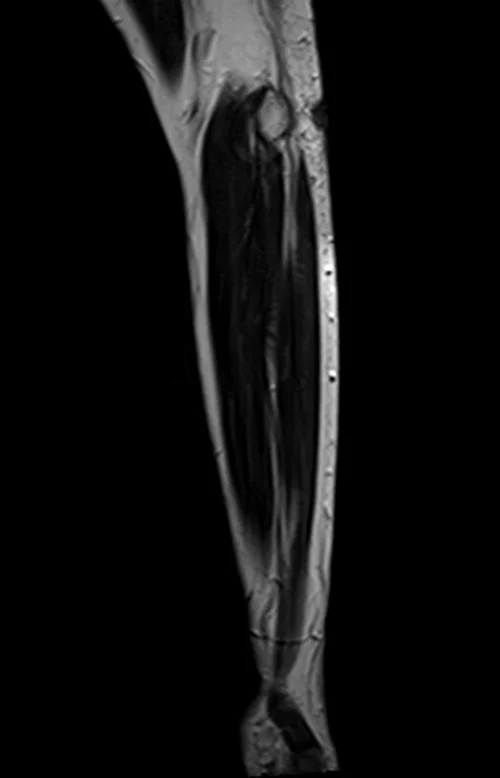

mri fore arm sagittal t2 image 2 - MRI